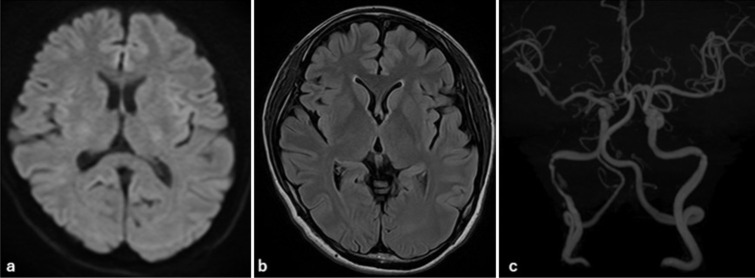

Case description: We report the case of a 45-year-old woman who presented with isolated right-sided glossopharyngeal nerve symptoms - specifically, ageusia and pharyngeal discomfort - along with mild posterior neck pain. Initial evaluation by otolaryngology failed to identify the etiology. Subsequent imaging at our hospital revealed a spontaneous dissection of the right internal carotid artery extending from the third cervical spinal cord level to the proximal petrous segment. Magnetic resonance angiography and digital subtraction angiography confirmed the diagnosis of ICAD. Conservative management with antiplatelet therapy (aspirin 100 mg/day) led to symptom improvement, and follow-up imaging after 180 days demonstrated near-complete resolution of the dissection.